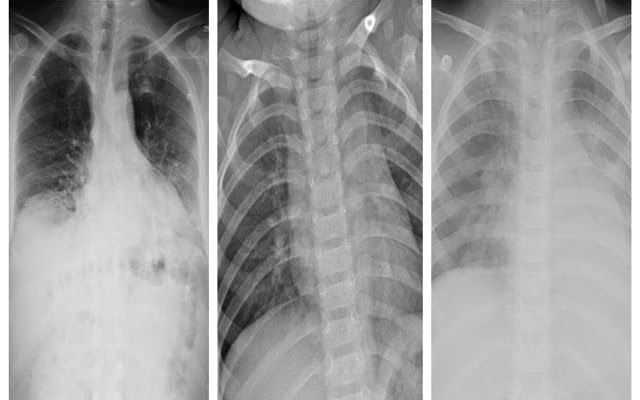

School of Engineering Team, Led by Karen Panetta, Uses AI and Machine Learning to Develop Software That Identifies COVID-19 Pneumonia